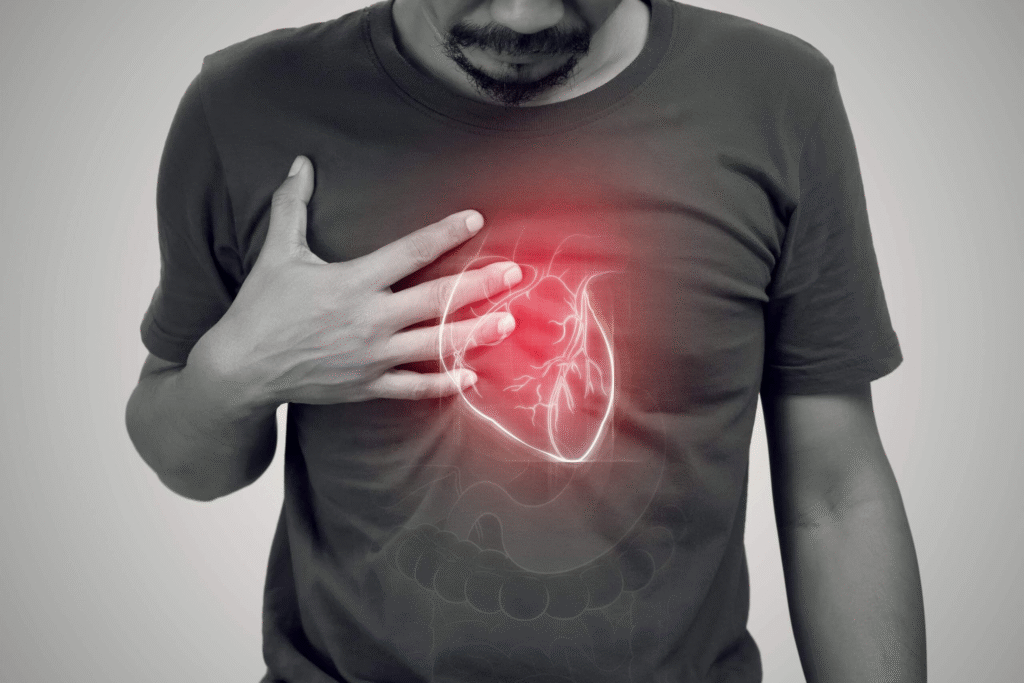

ਕੀ ਤੁਸੀਂ ਆਪਣੇ ਦਿਲ ਨੂੰ ਸਿਹਤਮੰਦ ਰੱਖਣਾ ਚਾਹੁੰਦੇ ਹੋ? ਜੇਕਰ ਅਜਿਹਾ ਹੈ, ਤਾਂ ਤੁਹਾਨੂੰ ਖੰਡ ਦਾ ਸੇਵਨ ਸੰਜਮ ਵਿੱਚ ਕਰਨਾ ਚਾਹੀਦਾ ਹੈ, ਨਹੀਂ ਤਾਂ, ਗੰਭੀਰ ਅਤੇ ਜਾਨਲੇਵਾ ਦਿਲ ਦੀਆਂ ਬਿਮਾਰੀਆਂ ਦਾ ਜੋਖਮ ਕਈ ਗੁਣਾ ਵੱਧ ਸਕਦਾ ਹੈ।